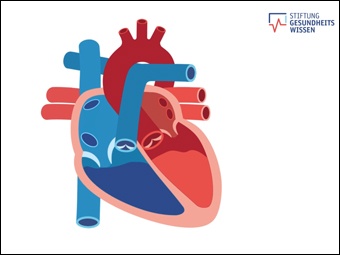

Wie funktioniert das Herz?

(öffentlich)

Online-Medium

(2020)

Anatomie des Herzens

(öffentlich) ZDF: Terra ...

Online-Medium

(2021)